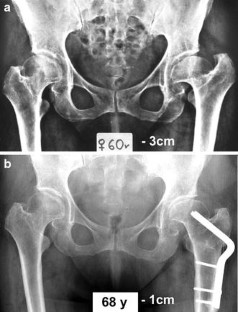

Fig. 2